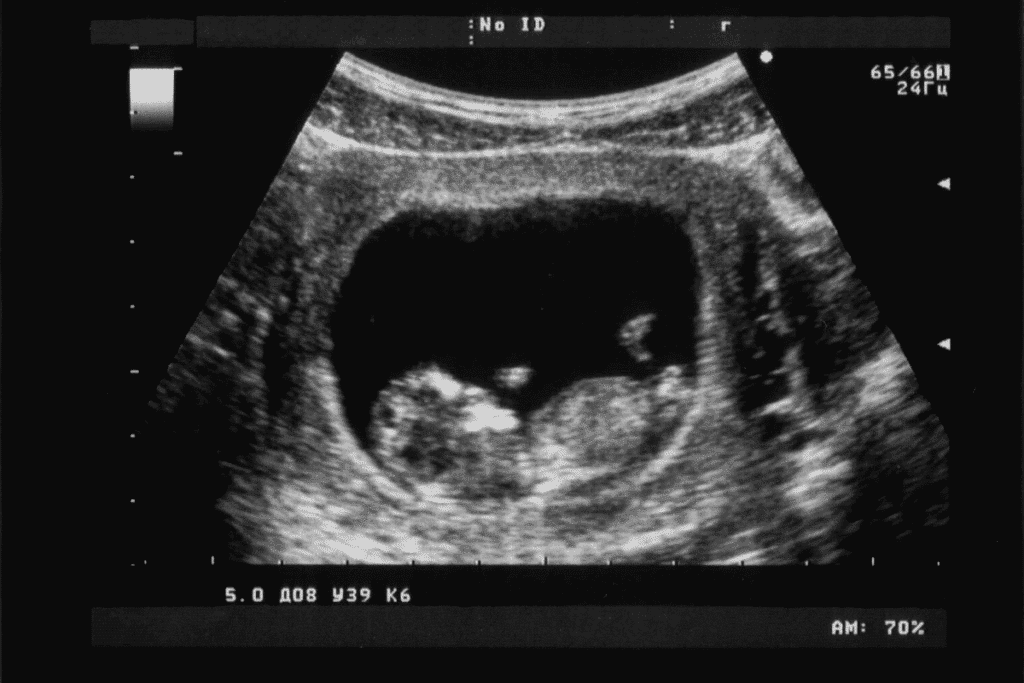

At 8 weeks, pregnancy is a big deal, and an 8 week ultrasound shows the baby’s first images. This scan lets us see important signs of a healthy pregnancy 8 week embryo ultrasound.

At this time, we can see the gestational sac, the baby’s outline, and its heartbeat. These details help us understand how the baby is growing. We measure the crown-rump length to figure out the exact due date.

At 8 weeks, an ultrasound shows important signs of a healthy pregnancy. We see key milestones that show how your baby is growing.

Gestational Sac and Yolk Sac

The gestational sac is seen early, around 4.5 to 5 weeks. By 8 weeks, it’s clear and holds the yolk sac. The yolk sac gives nutrients to the embryo before the placenta is ready.

The yolk sac is a key sign of the embryo’s health. Its size and presence tell us about the pregnancy’s chances.

Fetal Pole Identification

By 8 weeks, the fetal pole is clear, showing the embryo. It’s a thickened area on the yolk sac’s edge. It’s important for checking how the embryo is doing.

Amniotic Sac Formation

The amniotic sac is also seen at 8 weeks. It’s a fluid-filled space around the embryo. It protects the embryo as it grows.

Early Placental Development

Early placental development is seen at 8 weeks too. The placenta starts to attach to the uterus. It’s key for giving oxygen and nutrients to the embryo.

What Parents Can Expect to See

The 8-week ultrasound scan offers a unique look at the fetus’s growth. At this time, the fetus is about 1.22 inches long. It has reached many important developmental milestones.

The “Gummy Bear” or Bean-Shaped Appearance

One exciting thing parents see at 8 weeks is the “gummy bear” or bean-like shape of their fetus. The fetus looks like a bean, with a big head compared to its body. Early signs of limbs are also visible, showing the baby’s future growth.